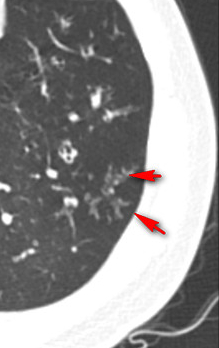

好在小夥肺功能雖然有阻塞,總體上沒有影響到生活,說話中氣很足,就是痰多,而且很難排出來,做了個胸部CT肺上面除了支氣管擴張之外,長了很多結節,就像一把“芝麻”撒在了肺上,有些芝麻恰巧撒在了擴張的終末細支氣管的旁邊,就像樹枝上發出的芽,所以稱為“樹芽徵”。

很多看過我科普的朋友應該知道是什麼疾病了,集齊了鼻竇炎、大量痰、呼吸阻塞、支氣管擴張、樹芽徵等這幾個要素的肺病,診斷就已經很明確了,那就是瀰漫性泛細支氣管炎,這個病首先由日本學者報道,需要長期使用大環內酯類藥物(比如紅黴素、阿奇黴素)治療,這個病如果不認識他,很有可能被長期誤診為慢性支氣管炎或者慢性阻塞性肺病,如果認識了他就好診斷了,早期診斷沒有形成支氣管擴張的話,口服阿奇黴素效果很好,甚至能治癒。